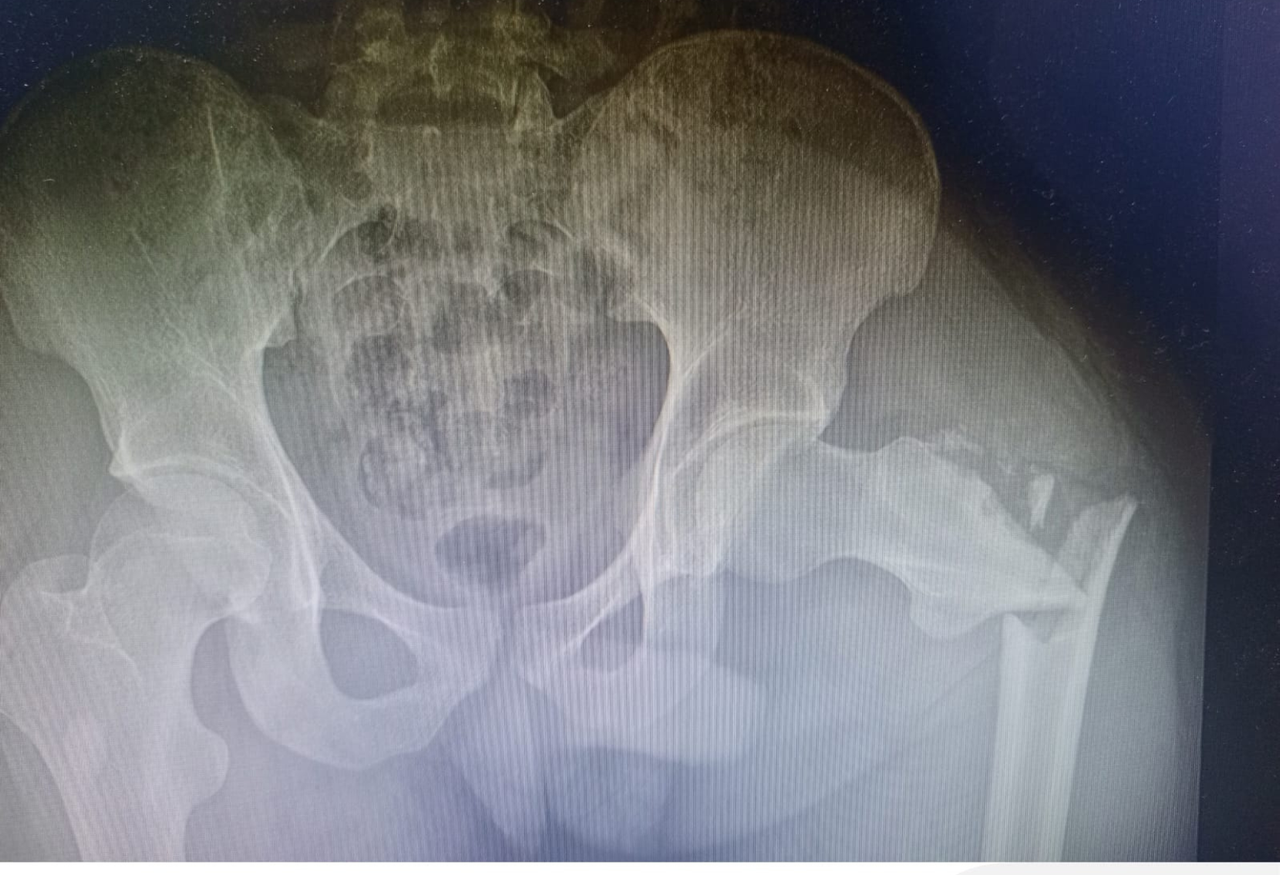

Fractura lateral de cadera izquierda

Ruptura del hueso en la parte externa de la cadera izquierda, generalmente causada por caídas o traumatismos, que provoca dolor y dificultad para caminar.

2

Cirugía exitosa

Se realiza reducción y aplicación de un DHS para estabilizar la fractura